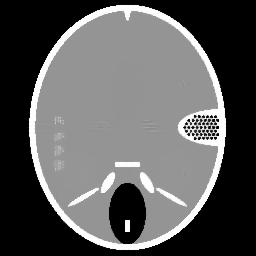

Figure 1. Phantoms for tests. (a) Head phantom used for simulation [24], (b) gel phantom used for real X-ray scan.

For the experiments, we test our method on a simulated head phantom from [24] and a real gel phantom shown in Figure 1. Here, we consider a 2D CT scenario. The detector has full coverage of the object at any projection angle, and a constant angular spacing of the rays is set in the interval of [0,π]0𝜋[0,\pi].

Example 2. Additionally to the simulated data, we also test our method on real CT measurements. In this experiment the gel phantom shown in Figure 1 (b) is measured using a fan-beam geometry with 560 beams and 360 or 180 projection angles. The reconstructions are in a square domain of 512×\times512 pixels, which result in an under-determined rate of 77% and of 38%, respectively.

In Figure 4 and 5 we compare our method with the FBP algorithm and the L2-TV method. Due to insufficient measurements and noise, FBP cannot provide satisfactory results. Comparing the results obtained by our method with the ones from the L2-TV method, we see that our method reduces more artifacts while keeping similar quality on reconstructed object textures. Furthermore, from the final values of λ𝜆\lambda obtained in our method we find that our method can correctly distinguish textured regions from homogeneous regions. Then, by setting different regularization parameter values, we vary the strength of the smoothness in the different regions.